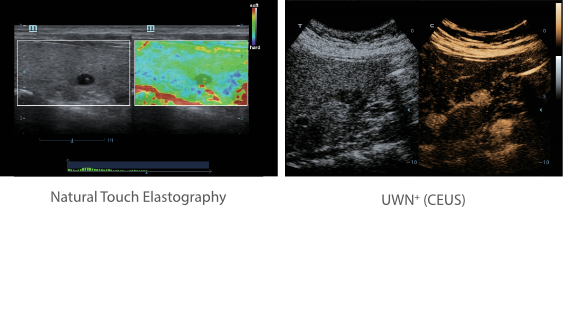

X-Insight is een inzichtelijke oplossing om meer visie te krijgen.

De gloednieuwe oplossing van Mindray is het geslaagde product dat is voortgekomen uit voortdurende klantinzichten in klinische behoeften in combinatie met steeds evoluerende, geavanceerde ultrasoundtechnologie?n. Vol energie en gebrand op toekomstgerichte inzichten en eindeloze mogelijkheden: dankzij de verhoogde schaalbaarheid wordt de oplossing continu verbeterd.

De DC-60 Exp met X-Insight is ontworpen op basis van diepgaand inzicht in klantbehoeften om hoge effici?ntie met nauwkeurige beeldverwerking te leveren, dankzij eXacte helderheid, eXceptionele intelligentie en eXcellente ervaring.